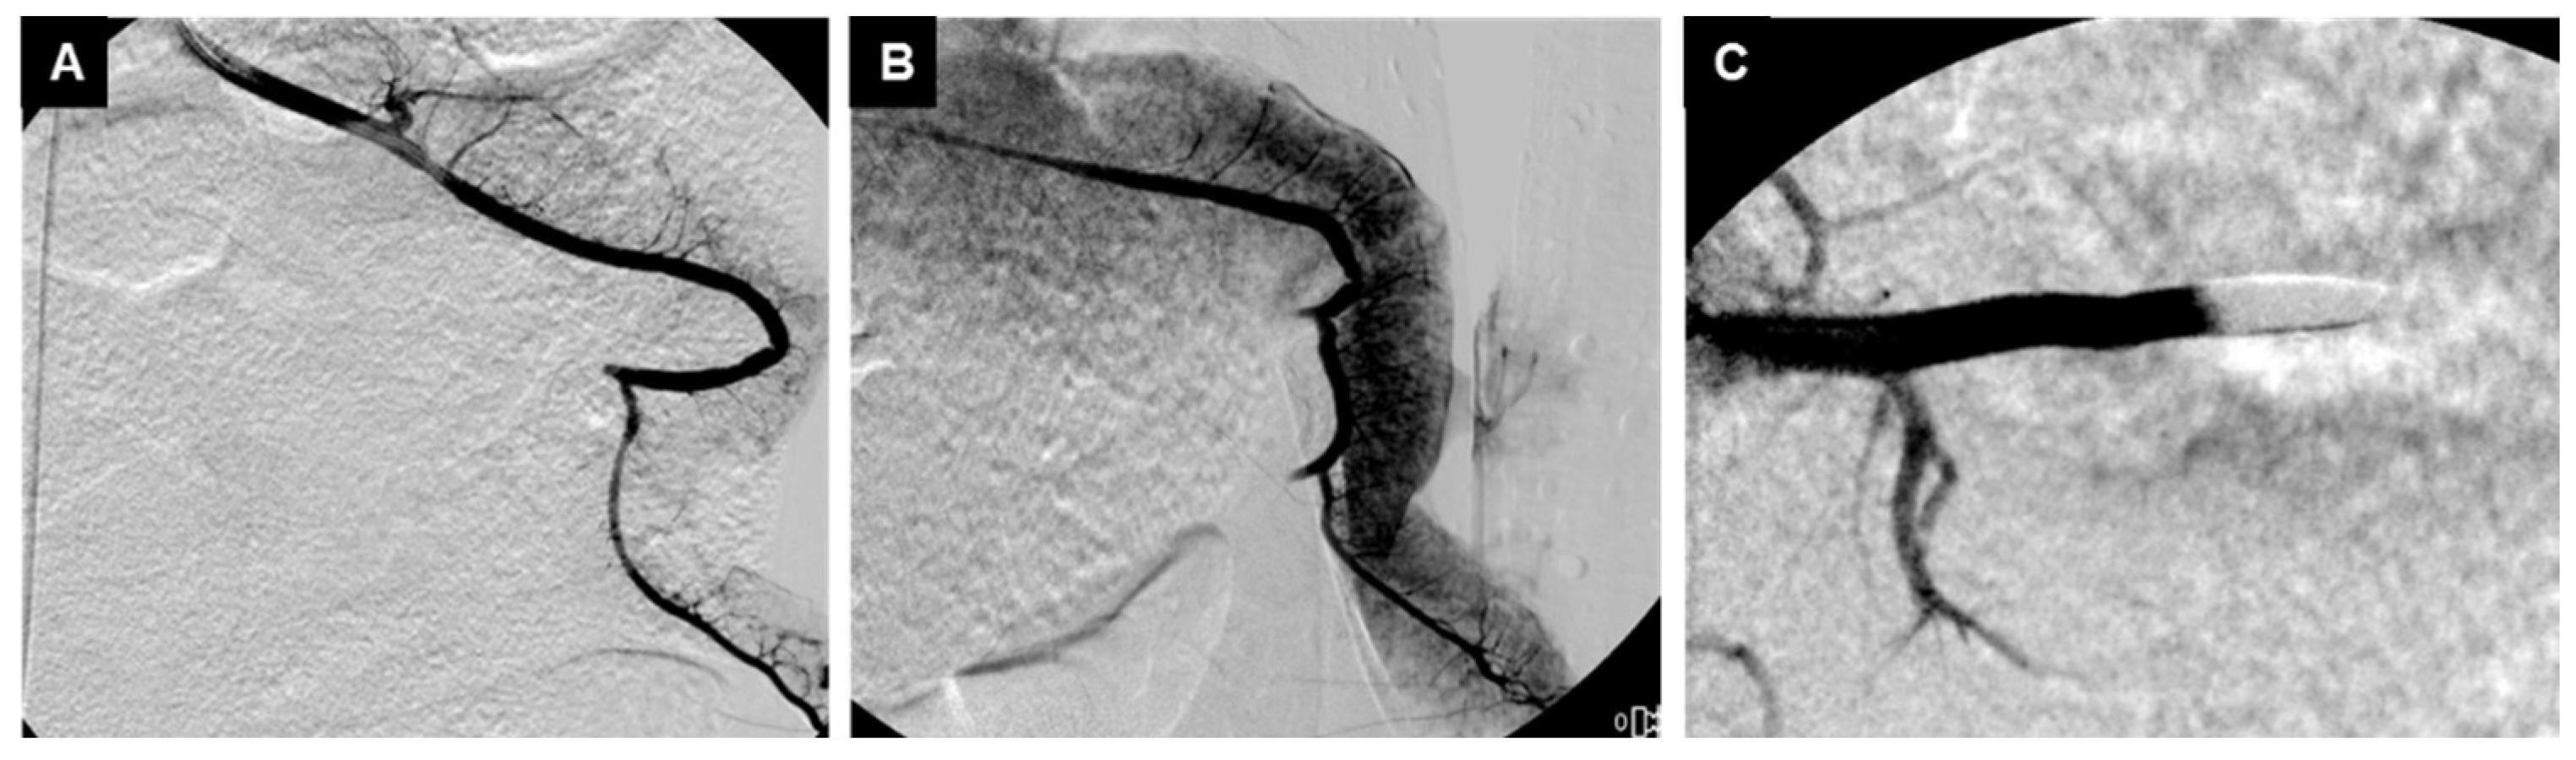

3.2. Embolization Procedure